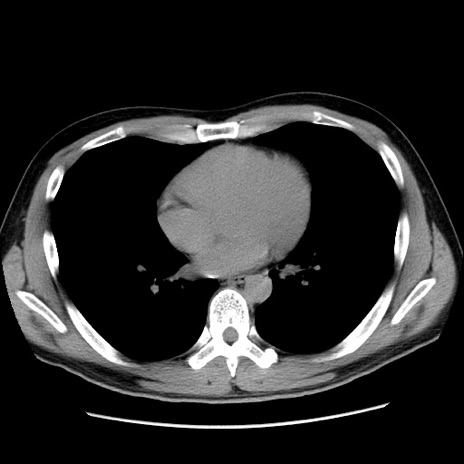

症例36(横断像)

冠状断像

【症例】20歳代 男性

【主訴】心窩部痛

【現病歴】今朝より上腹部痛あり。一旦軽快していたが再度出現したため救急要請。昨日夕に白身の魚を含む刺身を食べた。

【身体所見】BP 136/89mmHg、HR 74/min、BT 37.0℃、腹部:膨満、軟、心窩部に圧痛あり。反跳痛なし、筋性防御なし、腸雑音やや亢進あり。

【データ】WBC 17700、CRP 0.48